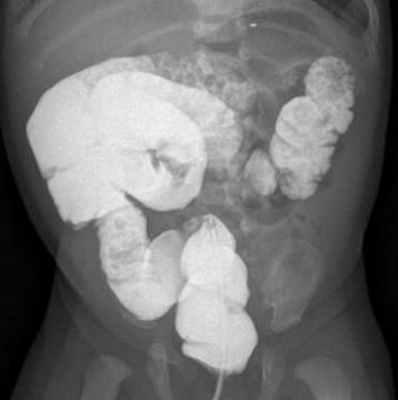

Следующий тип мальротации характеризуется наличием только двух поворотов вместо естественных трех, горизонтальная часть двенадцатиперстной кишки вращается позади оси брыжеечных сосудов, короткий корень брыжейки не прикреплен, вследствие чего могут возникать связки Ледда. На ирригограмме слепая кишка и восходящий отдел толстой кишки расположены высоко, смещены несколько правее от позвоночного столба (рис. 2, 3).

Рис. 3. Ирригограмма в прямой проекции. Отмечается расположение петель толстой кишки преимущественно в правом фланке брюшной полости